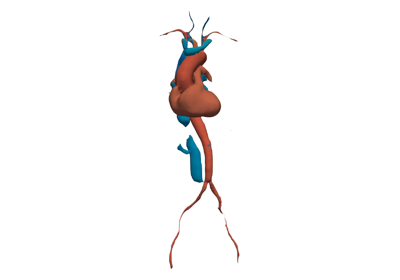

Here is a gallery of several examples demonstrating what PyVista can do.

Include here are few longer, more advanced examples from our users and developers.